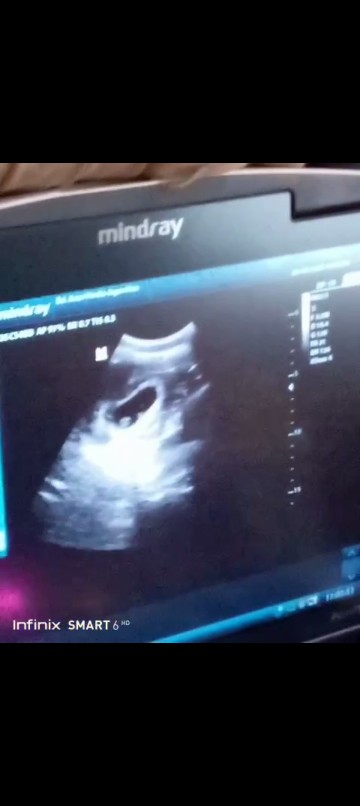

sy 8minggu bun baru segini sekitar 1.5 cm. alhamdulillah keliatan walaupun blum jelas

bun ini punya saya 8week6day apa normal ya aku usg nya ke bidan krn spog jauh tp kenapa djj nya gk kedengeran dan aku tanya usia sgtu wajar tdk segitu wajar katanyaa..bun bener gk ya aku takut soalnya flek terus...mau k spog juga kdu uang banyak